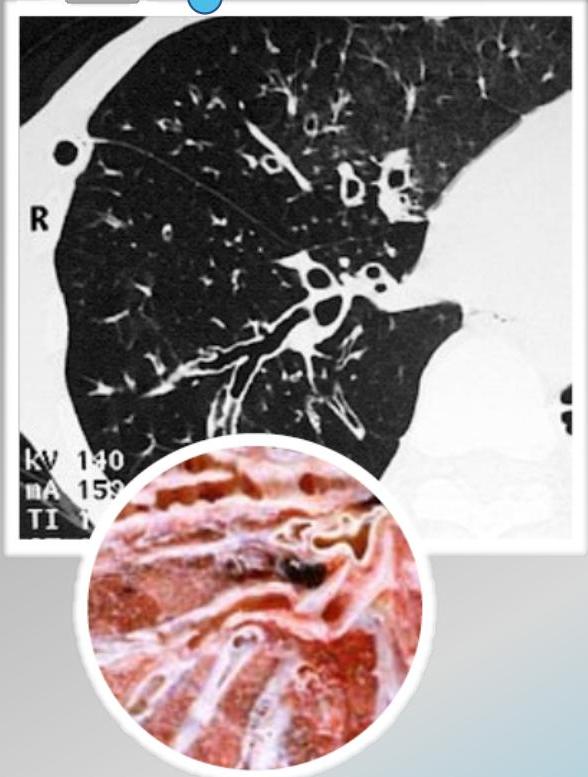

- ☐ Thin-section HRCT scanning: is the gold standard, with excellent sensitivity and specificity.

- ☐ Chest X-ray: increase in size and loss of bronchovascular markings, crowding of bronchi, and loss of lung volume. Severe case: Honeycombing.

Radiographic Findings (Chest X-ray)

Conglomerating cysts of varying size and wall thickness. “Honeycomb” sign.

Radiographic Findings (Signs)

Bronchial wall thickening and widening with parallel configuration. Tram track sign.

CT Scan Findings

Cylindrical

Saccular/Varicoid

Cystic

Signet Ring Appearance

CT scan showing bronchiectasis. Note the dilated bronchi with thickened wall, which are larger than adjacent arteries, giving a signet ring appearance.